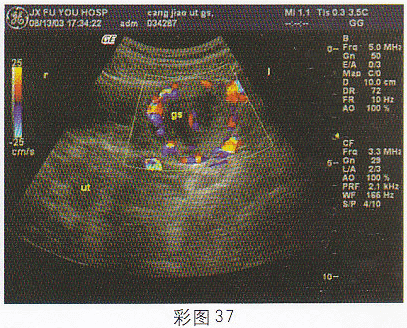

5.女,28歲,停經46天,陰道不規則出血5天。血HCG68μg/ml。結合超聲圖像(彩圖37),最可能的診斷為

正確答案:D 解題思路:附件區見囊實混合性光團,邊界尚清晰,子宮腔內有分離。患者有停經,不規則陰道出血,且血HCG增高。